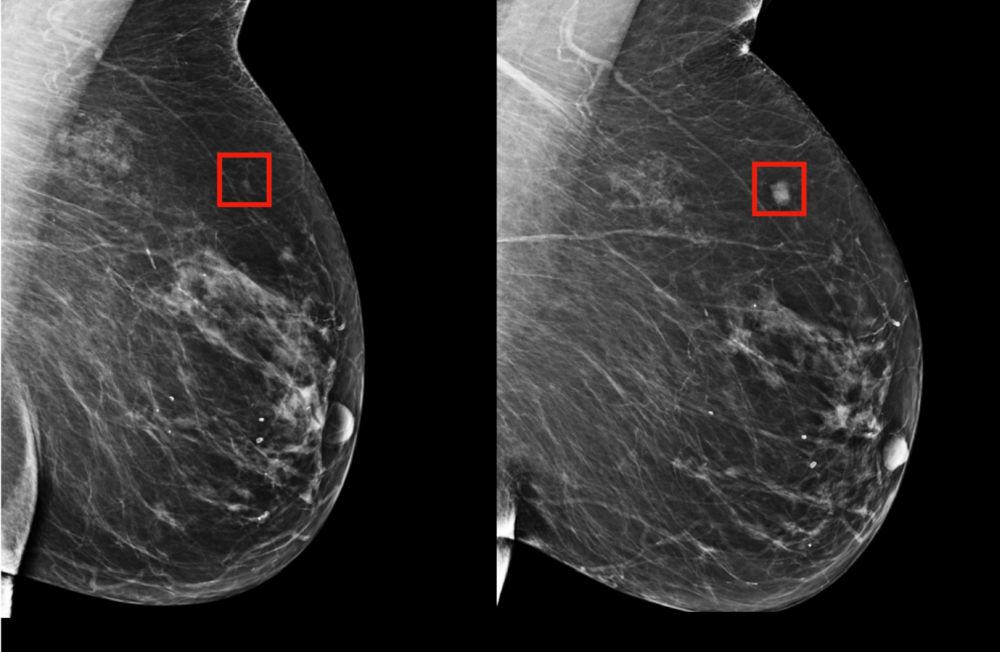

Mamograf odhalí nádor již v počátcích

Naprosto stěžejním vyšetřením je pak mamografický screening. Ten dokáže zobrazit patologické změny ve struktuře prsu, signalizující růst nádoru menšího než jeden milimetr. Tedy ve stadiu, kdy jej ještě nelze zjistit ani pohmatem.